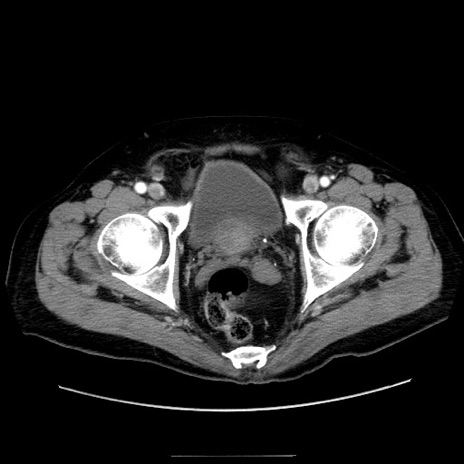

症例30(横断像)

【症例】80歳代男性

【主訴】臍周囲痛

【現病歴】約6時間前から臍下部痛が出現。次第に腹部膨隆・背部痛も生じてきたため来院。背部痛の場所は変化しない。

【身体所見】意識清明、BT 36.3℃、BP  131/87mmHg、P 87bpm、SpO2 100%(RA)、臍周囲自発痛・圧痛あり、反跳痛なし、自発痛部位に一致して板状硬あり、腹部膨隆、腸雑音減弱、CVA tenderness両側陰性。

【データ】WBC 19600、CRP 0.33

冠状断像